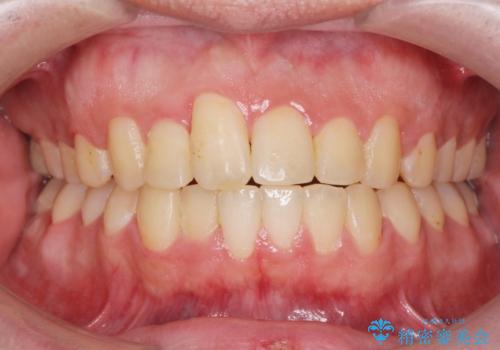

[セラミック治療] 前歯の審美治療に伴う矯正治療